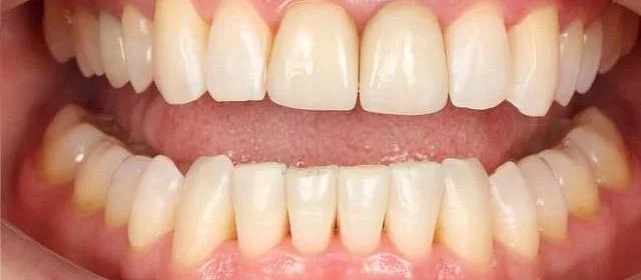

Результат

Зубы выровнены, скученность устранена, прикус исправлен, линия смыкания нормализована. Ретейнер установлен на нижнюю челюсть. На верхней ретейнер не ставили — на передних зубах коронки, вместо этого изготовлены ретенционные капы на обе челюсти. Пациентка направлена к ортопеду для замены коронок.

Решение: Поставили элайнеры Click на обе челюсти. Основной набор — 31 капа, плюс два дозаказа: 26 и 7 кап, итого 64. При этом лечение уложилось в 20 месяцев — быстро для такого объёма работы. Расширили дуги, убрали скученность, исправили прикус, выровняли линию смыкания. Ретейнер поставили только на нижнюю челюсть. На верхней от ретейнера отказались сознательно — на передних зубах коронки, и проволока там не ляжет корректно. Вместо этого изготовили ретенционные капы на обе челюсти. Ортопедию — замену старых коронок — пациентка будет проходить у себя в городе.

Непростой случай: II класс, сужение, скученность, деформация кривой Шпее и металлокерамические коронки на 11 и 21. Коронки ограничивают варианты ретенции — на верхней челюсти вместо ретейнера используем капы. Это осознанное решение, принятое совместно с пациенткой. 64 капы за 20 месяцев — хороший темп для такого объёма. Основной набор сделал базу, дозаказы довели до нормы.